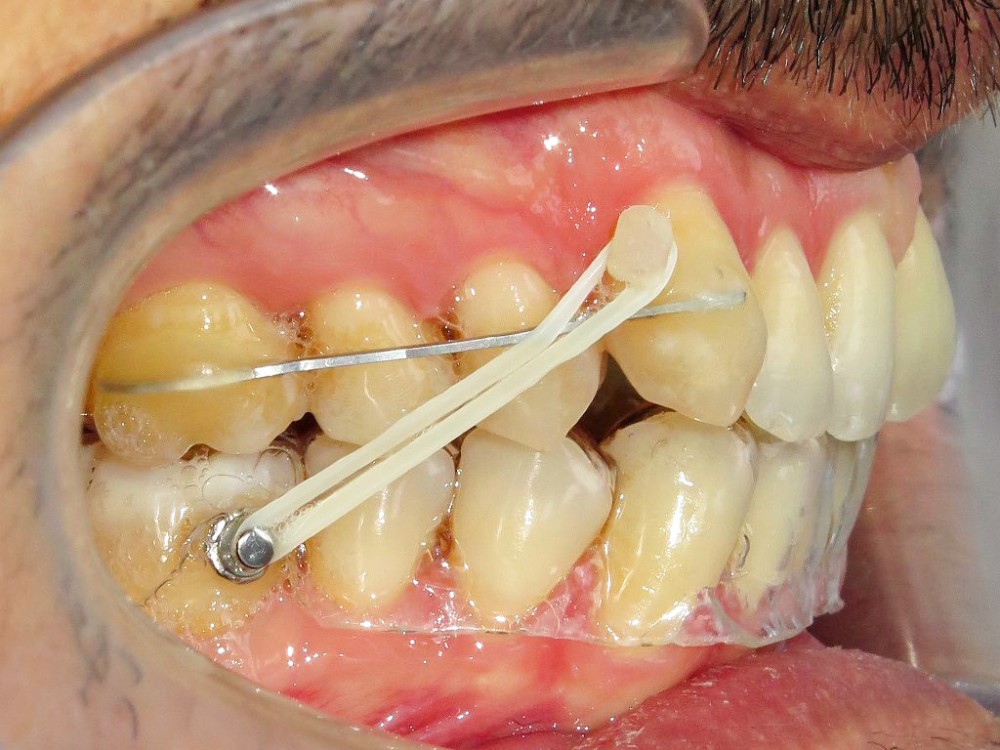

Dans un premier temps (fig. 2), la 28 (et la 18) a été extraite pour faciliter le déplacement de la 27 (DDM postérieure). Une minivis palatine a été placée entre 26 et 27 et des boutons ainsi qu’un sectionnel collés sur les faces vestibulaires des 26 et 27. Des chaînettes élastomériques ont été ancrées sur les boutons et la minivis, en passant au-dessous des faces occlusales de ces dents. Les chaînettes reliant un dispositif vestibulaire et un palatin et prenant appui sur les faces occlusales des molaires du secteur 2, les mouvements dentaires induits sont un déplacement vestibulo-palatin associé à une ingression des 26 et 27. Les minivis sont des ancrages absolus qui ne nécessitent pas d’utiliser l’ancrage des dents adjacentes ou antagonistes, ce qui préserve d’effets sur ces dernières.